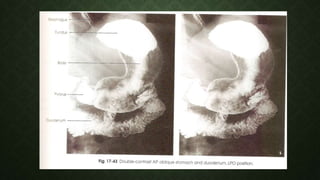

LEFT POSTERIOR OBLIQUE

(LPO)

(AP OBLIQUE)• Especially fundus

• Pyloric canal and

duodenal bulb

should be seen

without

superimposition